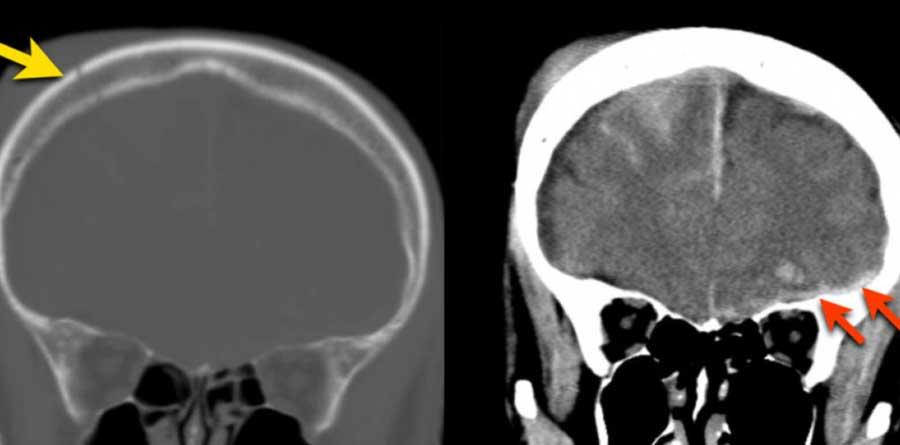

Đây là trường hợp tụ máu dưới màng cứng đồng tỷ trọng rất khó phát hiện (các mũi tên).

Lưu ý rằng ở mức cắt cao hơn có tụ máu dưới màng cứng hai bên.

Tụ máu dưới màng cứng có thể lan dọc theo liềm não và lều tiểu não như trong trường hợp này.

Các hình ảnh cho thấy máu tăng tỷ trọng trong khoang dưới nhện của rãnh Sylvius (mũi tên vàng).

Lưu ý xuất huyết dưới da đầu vùng chẩm phải (mũi tên xanh).

Đây là dạng tổn thương chấn thương kiểu coup-contrecoup.

Đây là một trường hợp chấn thương kiểu coup-contrecoup khác với các xuất huyết dập não và tụ máu dưới màng cứng ở thùy trán trái gần nền sọ (mũi tên đỏ).

Có xuất huyết dưới nhện bên phải kèm gãy xương đỉnh (mũi tên vàng).